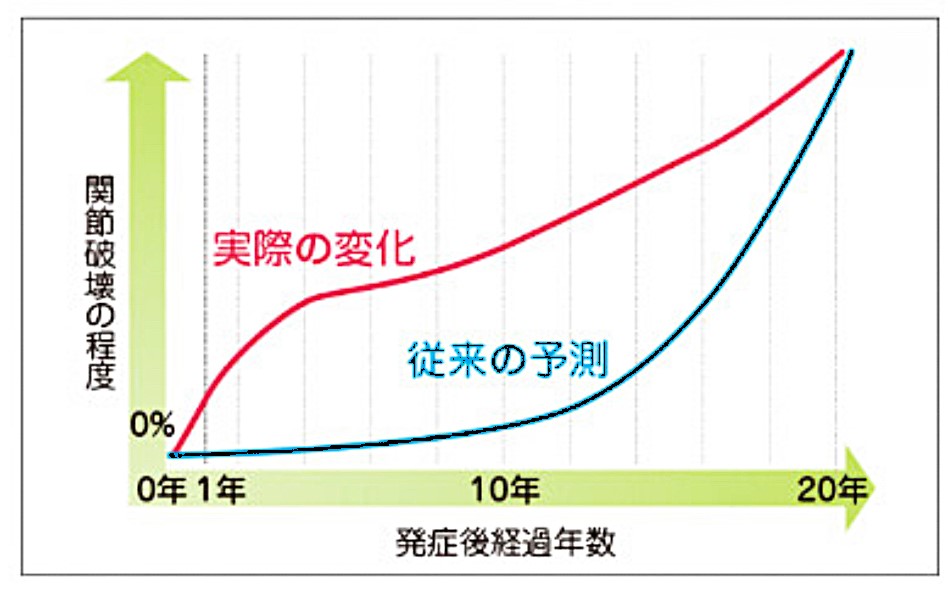

リウマチが進むと全身の関節に広がりうずくような痛みになります。治療しないと5年~20年で関節がこわれ人工関節や関節固定術などの手術が必要になります。

リウマチは診断が遅れれば遅れるほど難治性の炎症になります。最初の2年間が特に大切です。

数年治療が遅れると免疫の異常が強くなり治療に抵抗性になります。そのため軽い段階で見つけ治療を開始することが重要です。さらには関節注射やリハビリテーションを含めて総合的に治療できる整形外科医の役割が非常に高まっています。

血液検査でも陰性のリウマチが10%にあり陰性例では慎重な経過観察と積極的な治療トライも必要になります。画像検査のX線検査では関節裂隙狭小化や骨びらんなどのリウマチに特徴的な所見があります。しかしこれらは進行した状態で早期診断に有用ではありません。

当然このような状態になってしまっては進行しているということです。リウマチは早期診断が大切な訳で近年では超音波検査やMRI検査で滑膜炎の状態を診ることが重要になります。